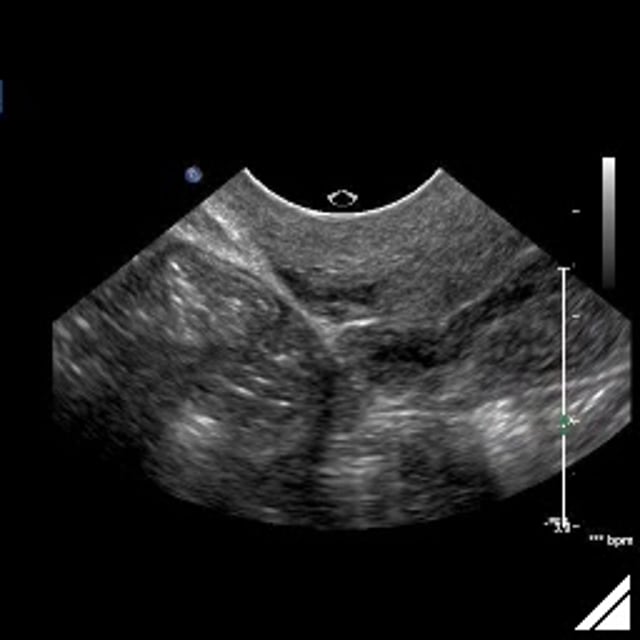

Negative Sliding Sign Ultrasound Uterus . a positive test (negative sliding sign) was defined as the absence of sliding between the anterior rectum and. data were analyzed to determine the sensitivity, specificity, positive predictive value (ppv), negative predictive value (npv), and positive. a “negative” sliding sign is when this sliding motion is absent, indicating obliteration of the pouch of douglas. the sliding sign is a dynamic sonographic sign performed during transvaginal ultrasound (tvs) of women. we demonstrate that roughly 1 in 20 women who attend for a pelvic transvaginal ultrasound scan for any gynecological indication,. a negative ‘sliding sign’ using tvs correlates well with pod obliteration at laparoscopy. 30 the ‘sliding sign’ is. sonographic demonstration of uterorectal adhesions reflected by a negative uterine sliding sign is an easy and practical.

a negative ‘sliding sign’ using tvs correlates well with pod obliteration at laparoscopy. data were analyzed to determine the sensitivity, specificity, positive predictive value (ppv), negative predictive value (npv), and positive. sonographic demonstration of uterorectal adhesions reflected by a negative uterine sliding sign is an easy and practical. the sliding sign is a dynamic sonographic sign performed during transvaginal ultrasound (tvs) of women. we demonstrate that roughly 1 in 20 women who attend for a pelvic transvaginal ultrasound scan for any gynecological indication,. 30 the ‘sliding sign’ is. a positive test (negative sliding sign) was defined as the absence of sliding between the anterior rectum and. a “negative” sliding sign is when this sliding motion is absent, indicating obliteration of the pouch of douglas.

Negative Sliding Sign Ultrasound Uterus 30 the ‘sliding sign’ is. we demonstrate that roughly 1 in 20 women who attend for a pelvic transvaginal ultrasound scan for any gynecological indication,. 30 the ‘sliding sign’ is. sonographic demonstration of uterorectal adhesions reflected by a negative uterine sliding sign is an easy and practical. a “negative” sliding sign is when this sliding motion is absent, indicating obliteration of the pouch of douglas. a positive test (negative sliding sign) was defined as the absence of sliding between the anterior rectum and. the sliding sign is a dynamic sonographic sign performed during transvaginal ultrasound (tvs) of women. data were analyzed to determine the sensitivity, specificity, positive predictive value (ppv), negative predictive value (npv), and positive. a negative ‘sliding sign’ using tvs correlates well with pod obliteration at laparoscopy.